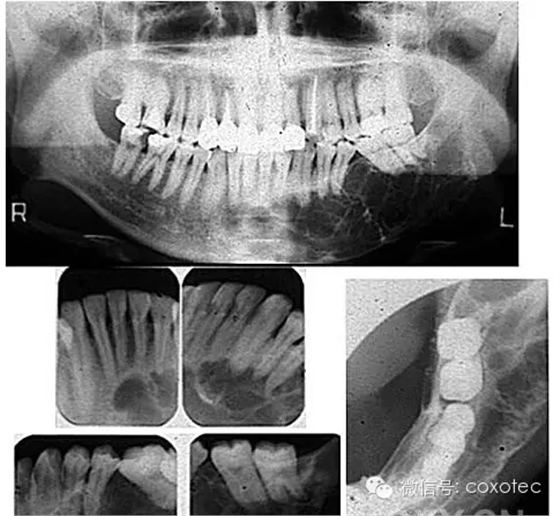

鎳鈦根管治療術(shù)是國(guó)際公認(rèn)現(xiàn)階段治療不可復(fù)性牙髓炎及根尖周?。ㄑ捞鄣闹饕颍┳顬閺氐缀童熜ё罴训囊环N方法,鎳鈦根管治療術(shù)通過(guò)清除根管內(nèi)的壞死物質(zhì),進(jìn)行適當(dāng)?shù)南?,充填根管,以去處根管?nèi)容物對(duì)根尖周?chē)M織的不良刺激,防止發(fā)生根尖周病變或促進(jìn)根尖周病變的愈合。

引進(jìn)根管治療儀是口腔內(nèi)科根管診療技術(shù)中的又一重大突破,鎳鈦合金材料引入牙科治療器械以來(lái),得到了長(zhǎng)足發(fā)展。20世紀(jì)90年代歐美率先用機(jī)器代替手工驅(qū)動(dòng)鎳鈦擴(kuò)大系統(tǒng)完成根管擴(kuò)大。醫(yī)生習(xí)慣將之稱(chēng)為“機(jī)擴(kuò)”。所具有的預(yù)備速度和質(zhì)量相較于傳統(tǒng)根管治療效率更高,效果更好,成形更好。并能最大限度的保存患者的牙齒,真正做到了事半功倍的神奇療效?,F(xiàn)代鎳鈦根管治療術(shù)把根管治療的水平提高到了一個(gè)新的臺(tái)階,并開(kāi)辟了牙髓病根尖周病等疾病治療的廣泛前景。

優(yōu)點(diǎn)二、維持根管形態(tài),維持根管彎曲度,減少側(cè)穿、臺(tái)階的發(fā)生;

優(yōu)點(diǎn)四、鎳鈦針的超強(qiáng)彈性和記憶合金特性,能順應(yīng)根管的彎曲進(jìn)行預(yù)備,不易折斷,適合于彎曲根管預(yù)備;